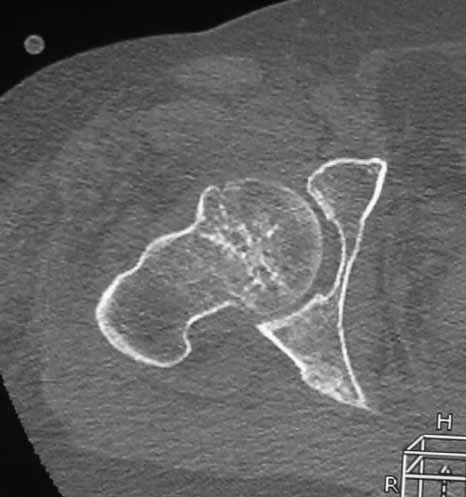

Пациентка 53 лет. ДТП 09.01.12: сочетанная травма: перелом 2-5 ребер справа, ушиб легких;

перелом обеих лонных костей без смещения; закрытый перелом проксимального конца правой

бедренной кости; открытый оскольчатый внутрисуставной перелом проксимальных концов

костей правой голени.

Бедро одномоментно делать не стал, не было уверенности в наличии перелома на уровне шейки. Во время операции смотрел тазобедренный сустав под ЭОПом,

головка неподвижна. После операции повторили КТ, стало очевидно, что имеется субкапитальный перелом. Что делать, остесинтез или протезирование? Если остеосинтез, то чем? Заранее благодарен за советы.